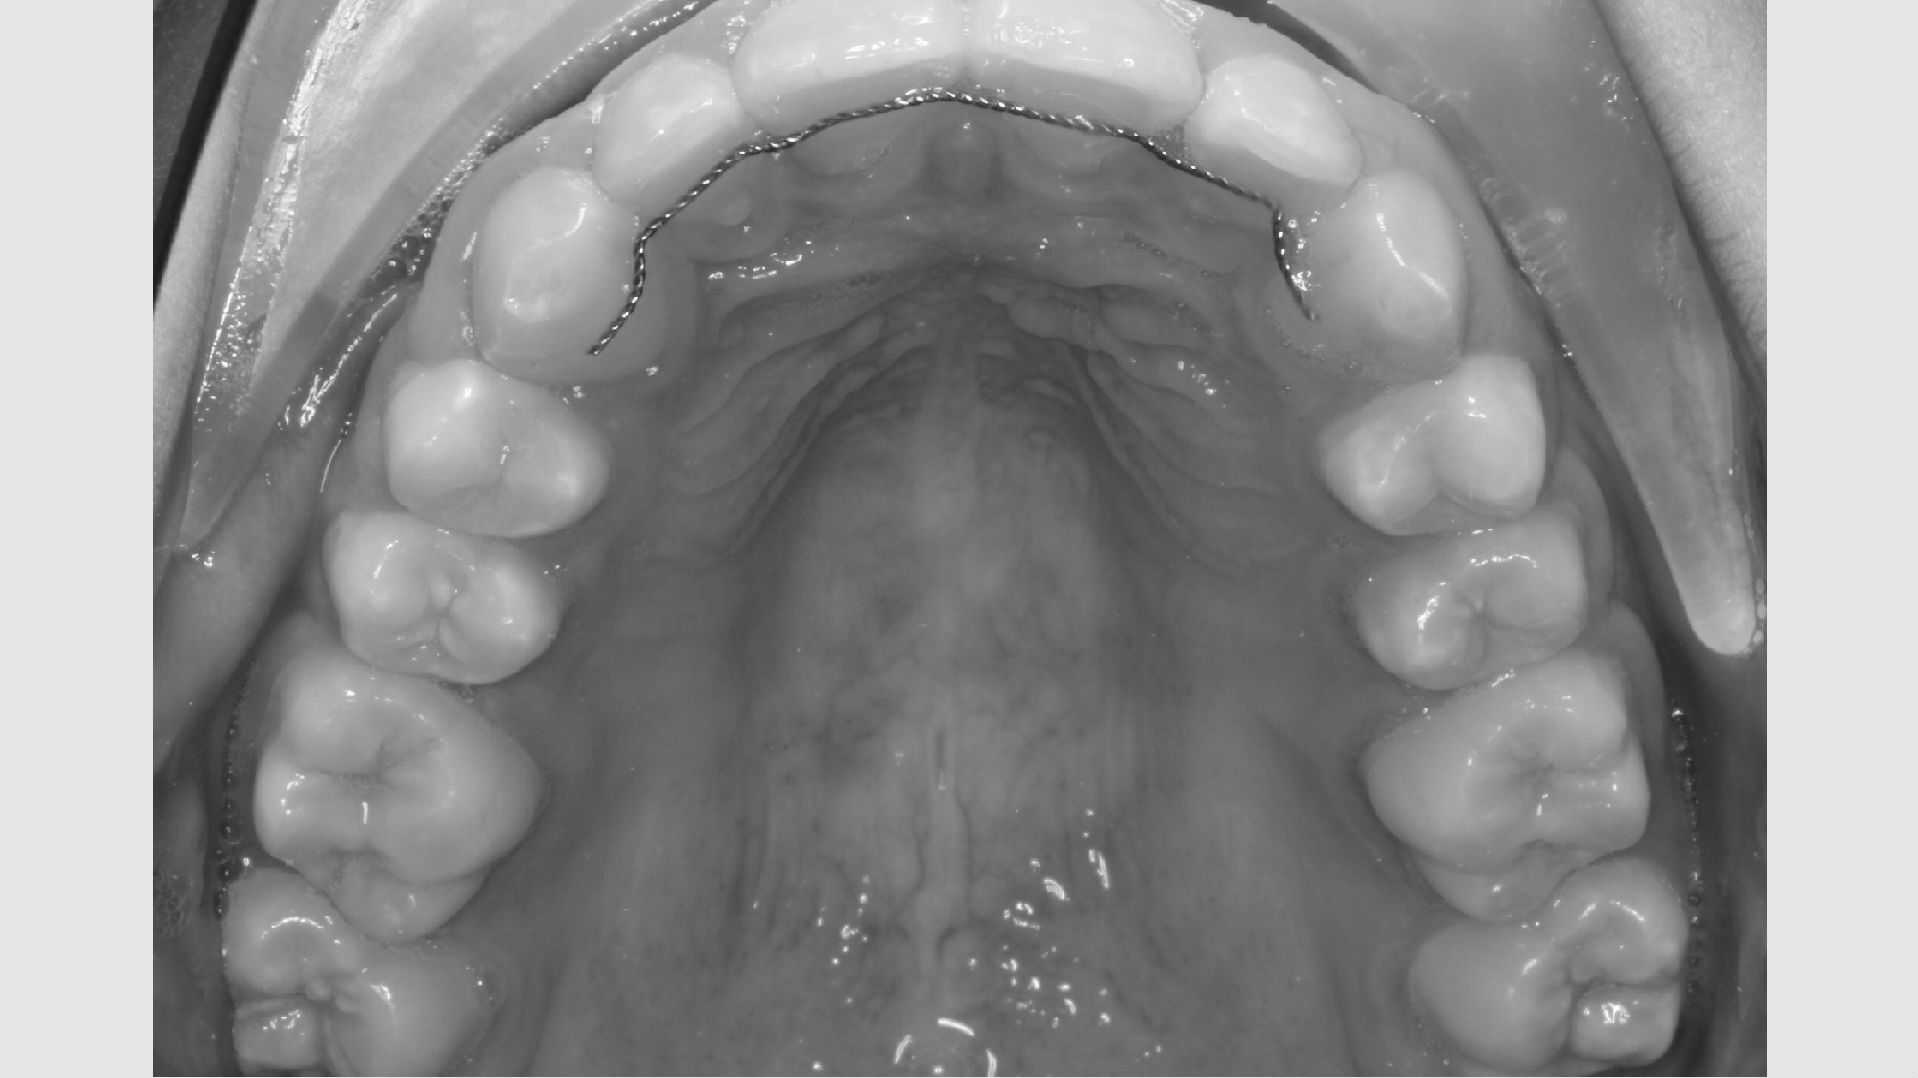

Der bliver taget billeder "udenpå og indeni" samt røntgenbilleder.

Dit barn skal selv holde sine læber til side med en læbeholder, mens tænderne bliver fotograferet. Billederne har følgende formål:

Det tager i gennemsnit 2 år at få rettet tænder med fast bøjle, hvorefter du får nogle holdebøjler. Der limes ofte en tråd bag på fortænderne i over- og underkæbe. Derudover får du en skinne eller plade til at sove med hver nat i omkring to år efter, bøjlen er taget af. Disse holdebøjler er vigtige at bruge og holde ved lige, hvis man ønsker at bevare tænderne i deres nye position.